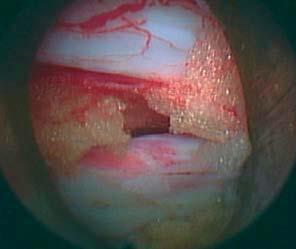

По направляющей спице вводится дилататор, в конечном положении он находится в позвоночном канале или дефекте фиброзного кольца. По дилататору вводится рабочая гильза, дилататор удаляется, скошенное отверстие находится внутри позвоночного канала дорсально относительно кольца.

Эндоскоп вводится через рабочую гильзу. Операция осуществляется через рабочий канал, распологающийся внутри эндоскопа с постоянной подачей жидкости, под визуальным контролем и при использовании сменных инструментов.